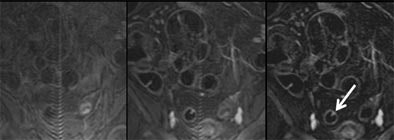

| Three views of the colon in a 48-year-old patient with a single polyp are seen at different time points: 1) without contrast material (left); and 2) following intravenous injection of 0.2 mmol/kg Gd-DOTA (Dotarem). This view shows good uptake of contrast material to the colon wall, and especially to the polyp (middle). Image at right 3) shows subtraction of the plain from the enhanced image, providing optimal visualization of regions with contrast uptake. Residual stool has also been subtracted, rendering the colonic lumen homogeneously dark. Images courtesy of Dr. Christoph Herborn. |